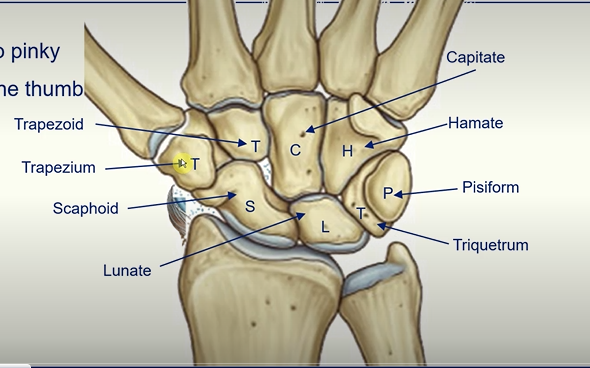

Carpal Bones -

Straight Line To Pinky

Here Comes The Thumb

Scaphoid

Lunate

Triquetrum

Pisiform

Hamate

Trapezoid

Capitate

Trapezium

The Anatomical Snuffbox

this region is highly palpated in order to see if the scaphoid bone is broken

the scaphoid bone has a good blood supply so if this is interrupted complications can occur

X - RAY